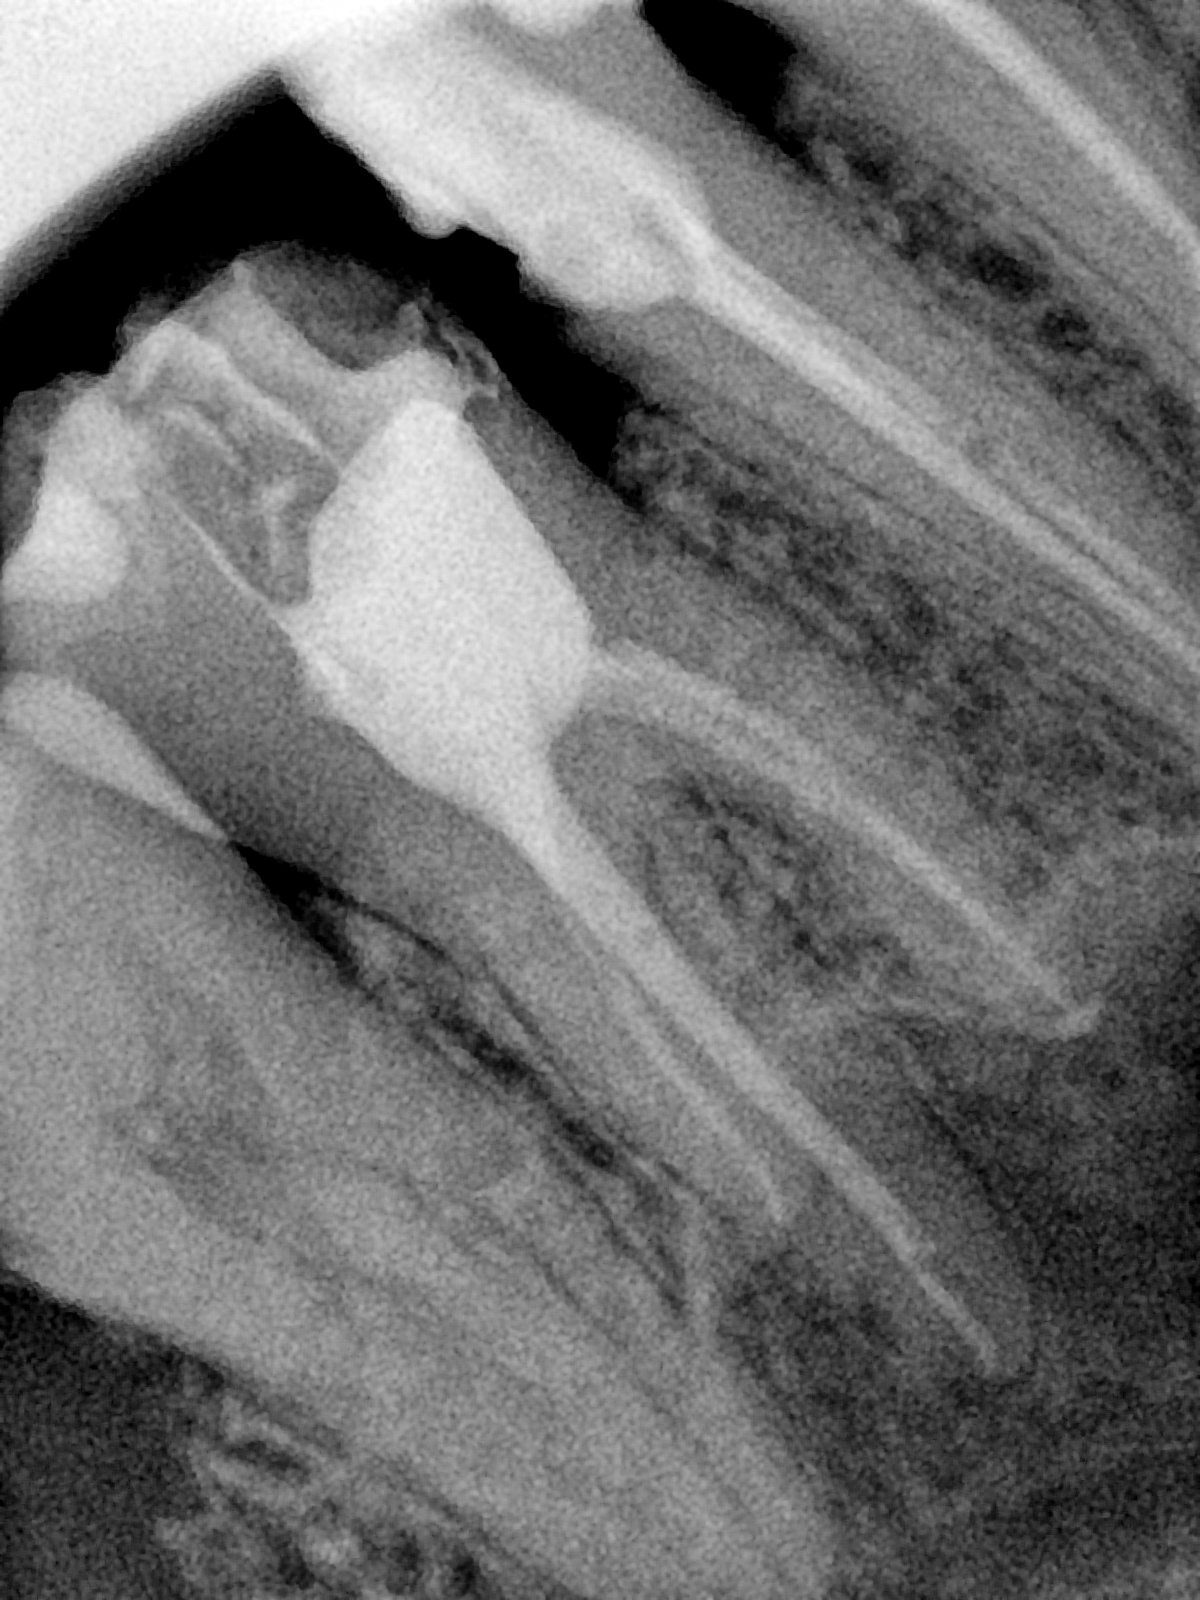

CR/DR 牙齿分割阶段记录

当前进展

- 完成了 CR/DR 牙齿相关分割训练

- 当前结果已经达到阶段预期,但仍有细节问题需要继续处理

相关测试

遇到的问题

- 训练过程中出现过 mask 下移问题

- 部分结果会出现 box 填充异常

- mask 边缘仍然有比较明显的锯齿感

参考

第二版算法问题测试

第三版算法分辨率效果比较

| 编号 | 原图 | 第一版 | 第二版 | 第三版 1216x1600 | 第三版 768x1024 | 第三版 1120x1120 |